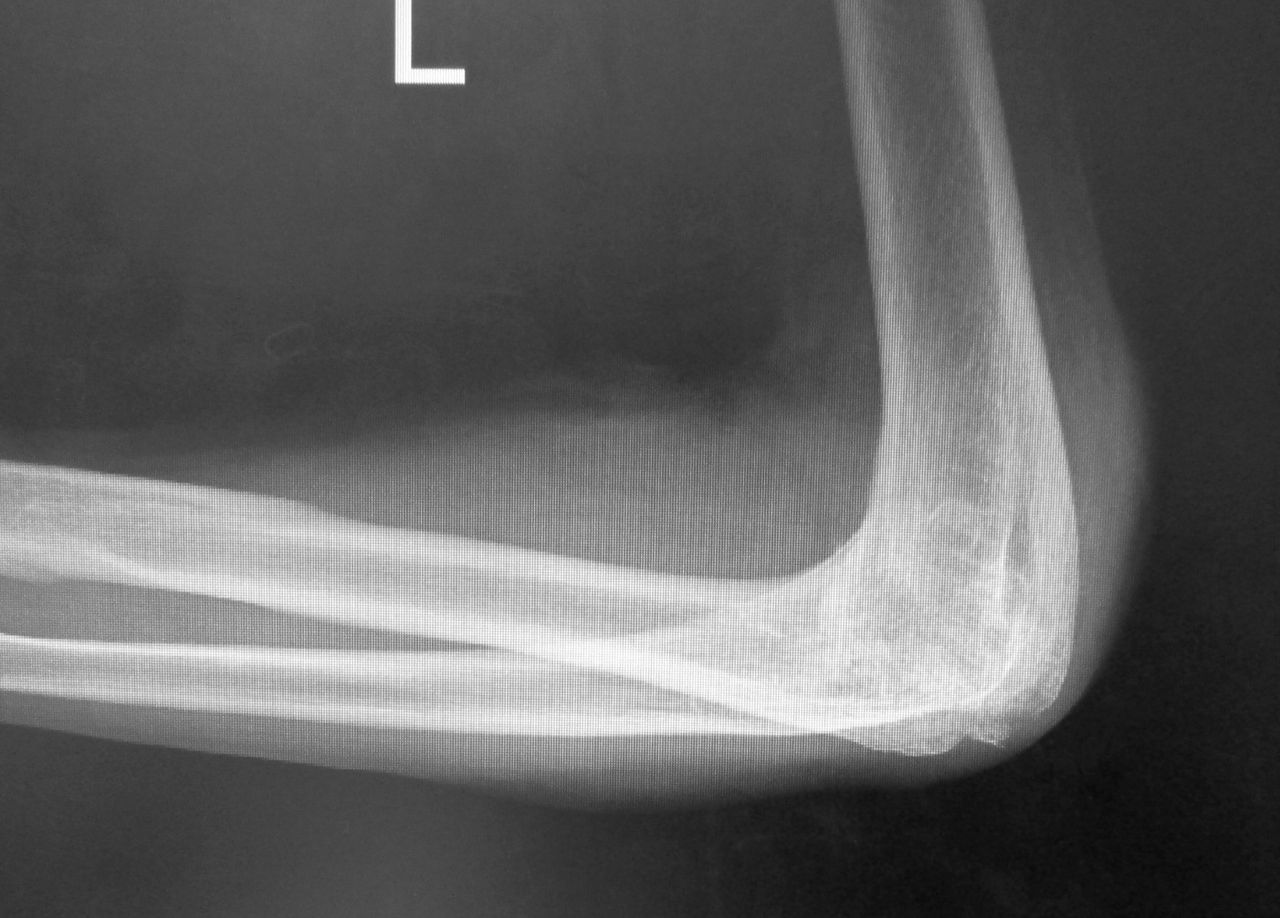

肘頭骨折 転倒して肘への直達外力 触診でほぼ診断可能だが 研修医 救急医のための整形外科 外傷 スポーツ医学マニュアル

肘頭骨折 尺骨近位端骨折

肘頭骨折 肘関節を伸ばせない 肘の痛みや腫れ 藤田鍼灸整骨院

肘関節 骨折 分類-肘をついて転倒すると骨折しやすい「 肘頭 」という部分があります。 読み方は 肘頭骨折 「 ちゅうとうこっせつ 」です。肘関節靭帯損傷 や、 モンテジア脱臼骨折 、 鉤状突起骨折 などの合併症を伴うことも少なくありません。 「肘頭骨折」の治療法は? 「肘頭骨折」の治療方法は、 ・保存療法 ・手術療法 に大別されます。 単純な肘頭骨折で、 骨折部の転位がない場合 には、

骨折のズレが そのまま肘関節の動きに悪影響を及ぼすということです。 肘頭骨折の症状とは? 肘頭骨折の症状としては、 まず当然ですが、肘の頭の部分の痛みです。 また、その周囲が腫れます。 肘の頭はすぐに骨が触れるくらいに 皮膚も、皮下脂肪も薄く、肘関節靭帯損傷 や、 モンテジア脱臼骨折 、 鉤状突起骨折 などの合併症を伴うことも少なくありません。 「肘頭骨折」の治療法は? 「肘頭骨折」の治療方法は、 ・保存療法 ・手術療法 に大別されます。 単純な肘頭骨折で、 骨折部の転位がない場合 には、